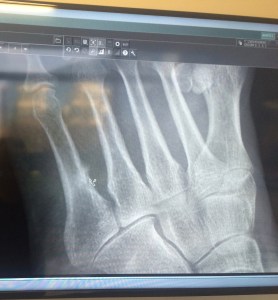

IMG_4659That’s my foot and that whitish area in the fifth metatarsal with the little arrow pointing to it is a stress fracture. I am now at the end of 6 weeks of wearing a boot and being on crutches.  I walked on the poor bone for a month before submitted — an absolute necessity in my view since to have dealt with it earlier would have meant cancelling a hiking trip to Italy (which I will blog shortly) and a trip to Durham both of which were greatly anticipated and worth the pain the required walking entailed.